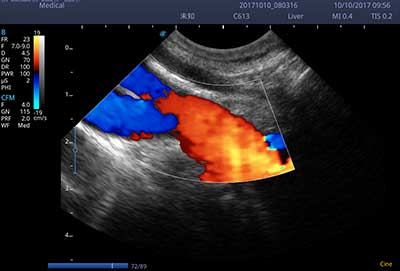

频谱自动包络